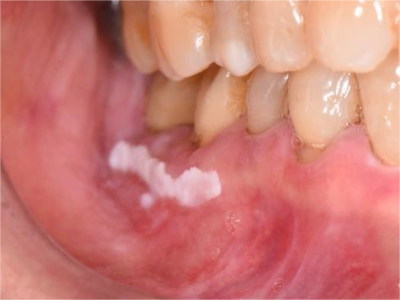

牙龈

白斑

口腔白斑病牙龈有一小块白色斑块图

口腔白斑病症状轻微时,患者的牙龈表面有一小块白色斑块,表现为轻度隆起或高低不平的损害形态,患处有木涩感,对冷热刺激和触觉不太敏感。